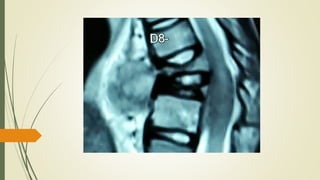

MRI Spine

• 37.